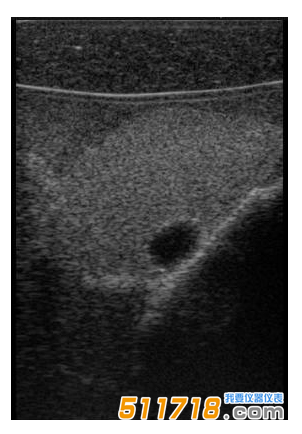

單純囊腫

CIRS 074甲狀腺超聲訓(xùn)練模體包含一個(gè)略微擴(kuò)大的甲狀腺,位于一個(gè)擬人化的頸部。下巴和鎖骨被提供作為外部解剖標(biāo)志。體模提供氣管,頸內(nèi)靜脈和頸總動(dòng)脈作為內(nèi)部解剖標(biāo)志。每個(gè)甲狀腺葉包含一個(gè)囊腫和一個(gè)等回聲僵硬病變。可以在甲狀腺內(nèi)定制生產(chǎn)各種結(jié)節(jié)。*有材料都配制成超現(xiàn)實(shí)的。

可以對(duì)每個(gè)囊腫進(jìn)行細(xì)針抽吸。每個(gè)僵硬病變都設(shè)計(jì)用于超聲彈性成像的可視化,并且可以進(jìn)行活組織檢查。這些病變對(duì)甲狀腺是等回聲的并且具有標(biāo)準(zhǔn)的B模式成像。